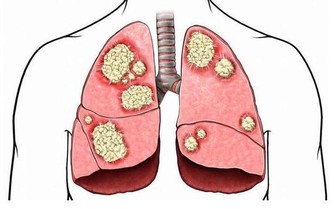

但如果莫名其妙出現尿頻尿急,夜尿增多,很可能是膀胱出現了惡性腫瘤或者是膀胱結石,導致膀胱儲存尿液的能力降低,伴隨著排尿頻繁的表現。

【4】糖尿病

夜間頻繁起身上廁所,也可能是糖尿病發出的信號,糖尿病並非普通的小疾病,一旦確診糖尿病,也是非常頑固、難以控制的。

在體內血糖不斷地升高的過程當中就會刺激,身體出現口乾舌燥的情況,需要身體及時補充水分,而大量攝取水分之後就會導致尿液增多,也希望大家通過合理的治療,保持血糖的穩定。